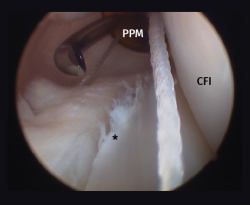

Other diagnostic tests are radiographs under stress varus conditions. We can find indirect radiological signs such as Segond fracture and the arcuate sign. MRI is of great help. Gelber et al. recently reported that over 80% of a group of world experts in the treatment of posterolateral angle injuries agree on the usefulness of MRI in the diagnosis of these lesions(17). Lastly, arthroscopy can offer additional information in the surgical cases (Figure 2).

Figure 2. Arthroscopic view through the anterolateral port of damage to the meniscus-popliteal ligaments (*) at the level of the popliteal hiatus, leaving the tibia exposed (T). P: tendon of the popliteus muscle. Right knee.